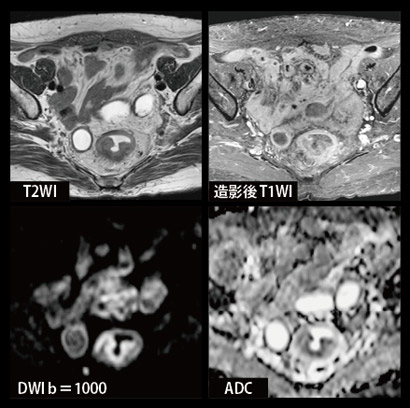

快適性だけでなく,画質も安定して得らており,Teratoma(奇形腫)(図1)症例でも,スピンエコー系のT1強調画像,T2強調画像において,骨盤部の均一な画像が得られていました。液体の中に多数漂っているのは,脂肪を含んだ組織です。1回の撮像で,In-phase,Opposed-phase,脂肪抑制,水抑制の4種類の画像が同時に得られる,DIXON法に基づいたVIBEシーケンスの有用性も紹介されました。ボール状の組織がOpposed-phase画像で低信号となっていますが,これは水由来,脂肪由来の組織が混ざり合っていることを示しているそうです。また,腸内の空気の影響により歪みが大きくなりやすいとされる直腸の拡散強調画像も,均一な脂肪抑制とともに歪みのない画像が得られていました(図2)。

図2 直腸がん症例(69歳,女性)